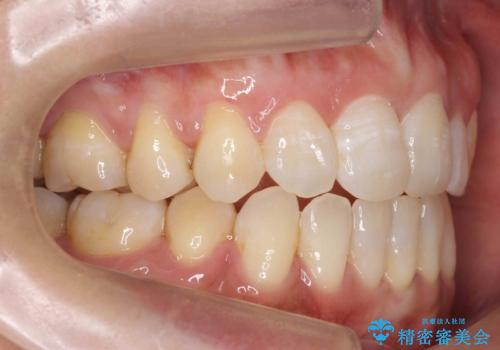

- 前歯の重なりを主訴に来院。

前歯が顔の真ん中に飛び出しているような状態でした。

右上の犬歯が奥深く埋伏していました。

成人の矯正でしたので、矯正治療前にしっかり必要な歯周病治療を行い、状態が改善してから開始しました。